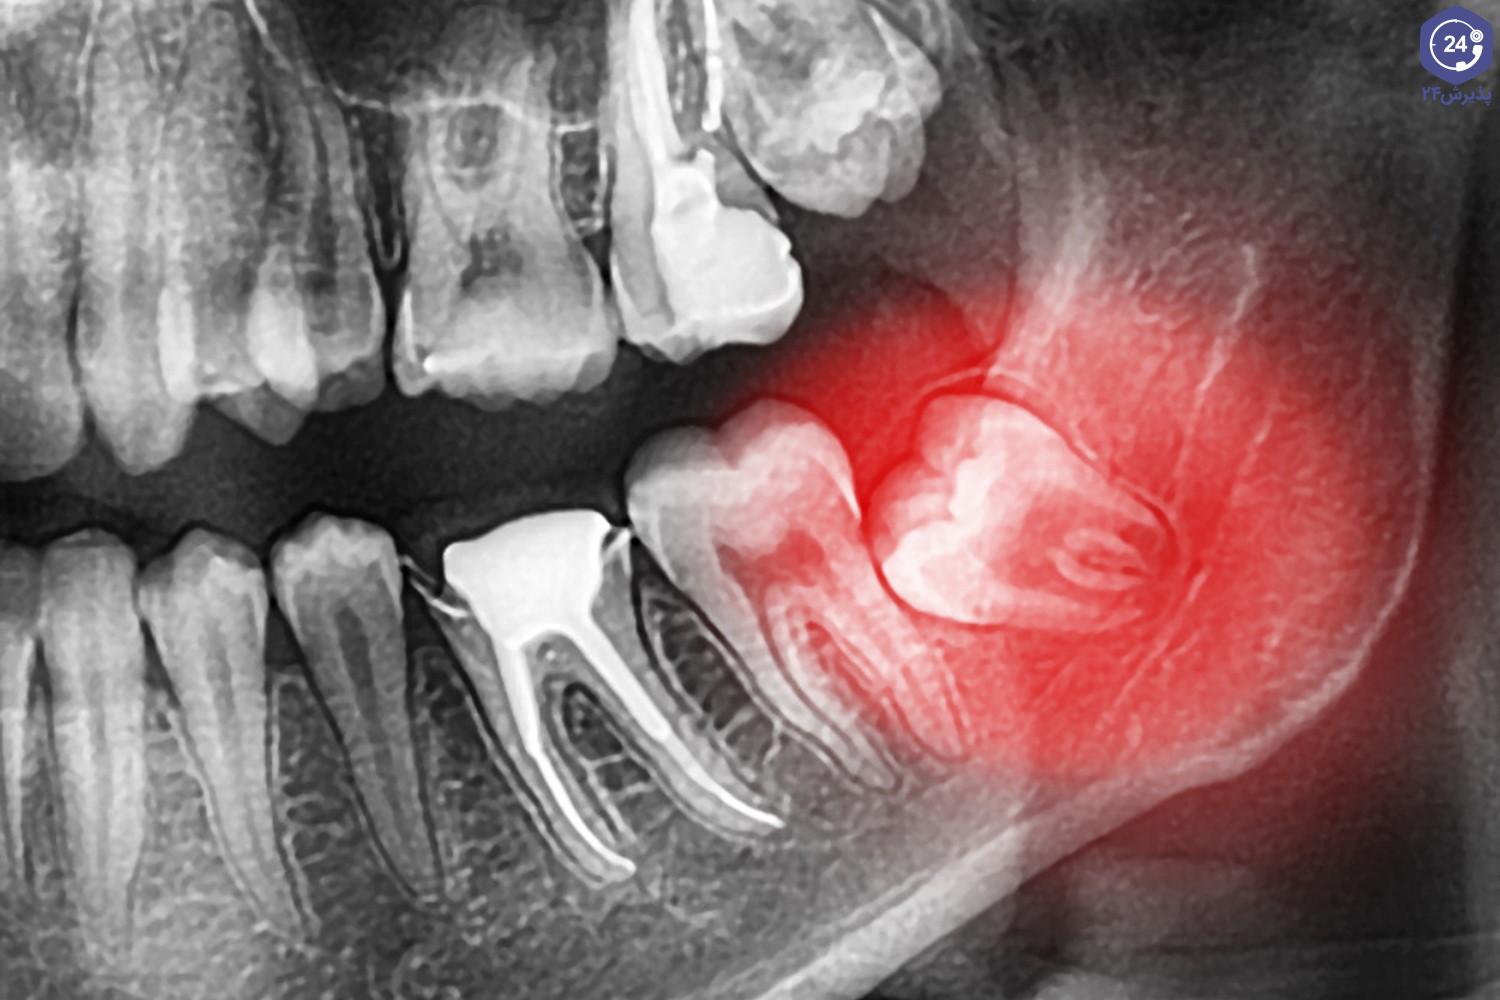

دندانهای نهفته معمولاً به دلیل عدم رویش کامل در فک یا فضاهای محدود در دهان، در زیر لثه گیر میکنند. علائمی مانند درد مزمن، التهاب لثه، ایجاد کیست یا عفونت، و یا فشار به دندانهای مجاور از جمله علائم دندان نهفته هستند.

دندانهای نهفته میتوانند باعث مشکلات متعددی مانند:

عفونتهای مکرر

درد شدید

ایجاد آسیب به دندانهای مجاور

به هم ریختگی ساختار دهان و فک